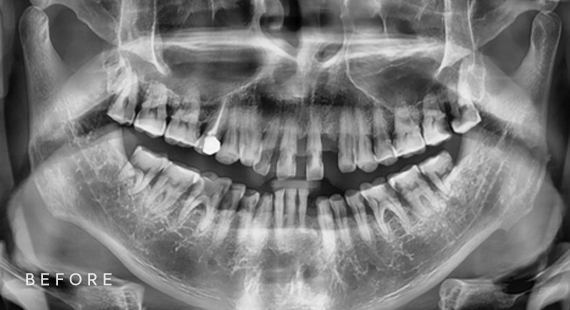

임플란트

충치치료

신경치료

사랑니 발치